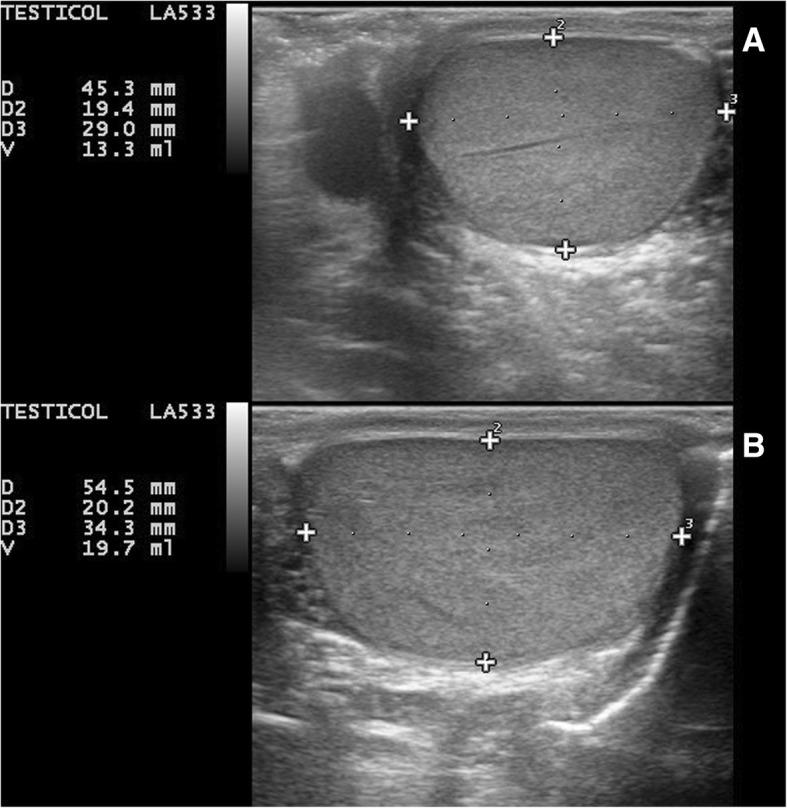

We report the case of a pubertal boy affected by BWS, who developed a progressive testicular enlargement, ipsilateral to the pre-existing external body overgrowth. Asymptomatic unilateral testis enlargement started after regular pubertal onset and worsened over time, without any associated pathological findings in a long-term follow-up. Since biopsy is not indicated in case of benign macro-orchidism, we hypothesize that this asymmetric enlargement could be an expression of visceral lateralized overgrowth in BWS.

At the best of our knowledge, this is the first detailed report of unilateral testicular overgrowth in BWS. We revised common causes of painless unilateral scrotal masses in the pediatric age. Considering both the overall frequency of neoplasia and the malignancies predisposition in BWS, a testicular cancer should be carefully ruled out through a close follow-up, before stating a benign condition. A normal ultrasound pattern, together with normal serum hormonal levels and negative tumor markers, make testicular neoplasms highly unlikely.

我们报告了一例青春期男孩患 BWS 的病例,他出现了进行性睾丸增大,同侧存在先前存在的外部身体过度生长。在定期青春期开始后,无症状性单侧睾丸增大开始,并随时间恶化,在长期随访中无任何相关的病理发现。由于良性巨睾症不需要进行活检,我们假设这种不对称性增大可能是 BWS 内脏单侧性过度生长的表现。

据我们所知,这是首例 BWS 单侧睾丸过度生长的详细报告。我们复习了儿科时期无痛性单侧阴囊肿块的常见病因。鉴于 BWS 中肿瘤的总体发生率和恶性肿瘤易感性,在确定为良性疾病之前,应通过密切随访仔细排除睾丸癌。正常的超声模式、正常的血清激素水平和阴性的肿瘤标志物使睾丸肿瘤极不可能。